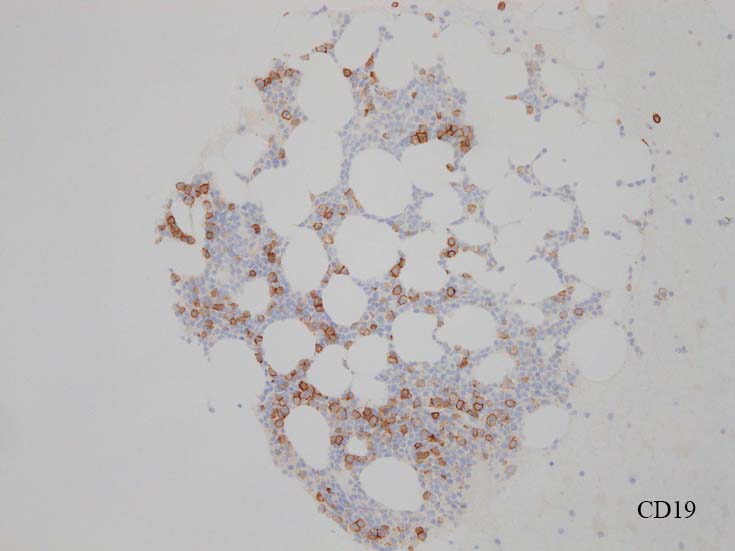

blastic cellsは, CD45+, CD34+, CD38+, TdT+, CD7+, HLA-DR+, CD123+. cCD3-, sCD3-(FCM), CD20-, CD19-とCD79a-(?) (plasma cellが陽性でIHCでは判定が難しい), MPO-.

CD3-, CD79aは増加しているplasma cellsが陽性で判定が難しい. CD10-, MPO-. (CD10は画像欠)

CD138陽性細胞が増加している. CD19陽性細胞が多く認められ, 明かなkappa, lambda restrictionは見られない. polyclonal proliferationと考えられる.